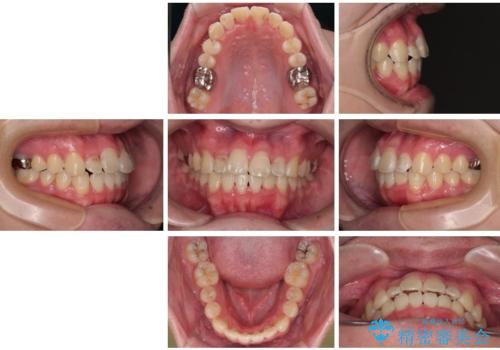

適切な診断と装置の選択により、1年という短期間でここまで改善できます。

見た目の美しさだけでなく、将来のむし歯や歯周病リスクを減らすことにもつながる治療です。